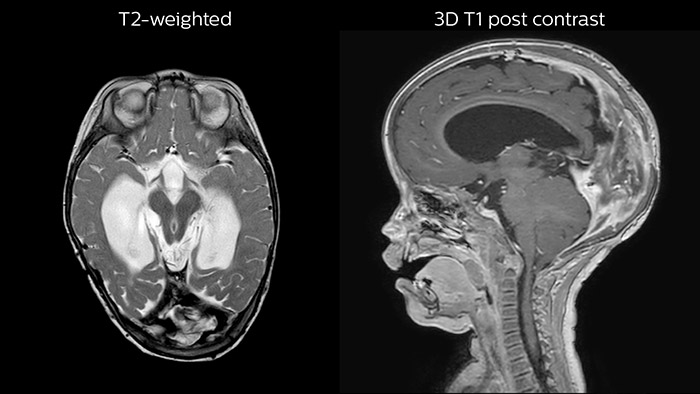

Since scan times of 3D scans can be significantly shortened thanks to Compressed SENSE, the MRI team is performing more 3D scans than before. “The advantage of 3D scanning is that we capture one high resolution sequence, but we can reconstruct images in any orientation, even after the scan, when looking at the images for diagnosis. Having this ability to view any crosssection we need in high resolution, can make re-scanning unnecessary,” says Dr Junge. “We are currently optimizing our routine head examination to include more 3D scans, including T1- weighted, T2-weighted and FLAIR.”

Hydrocephalus post hemorrhagic

Both pictures show a ventriculoperitoneal shunt. With our previous scanner our hydrocephalus protocol needed about 25 min. With Ambition the examination time is about 14 min. including a CSF PCA sequence to show flow in the aqueduct.